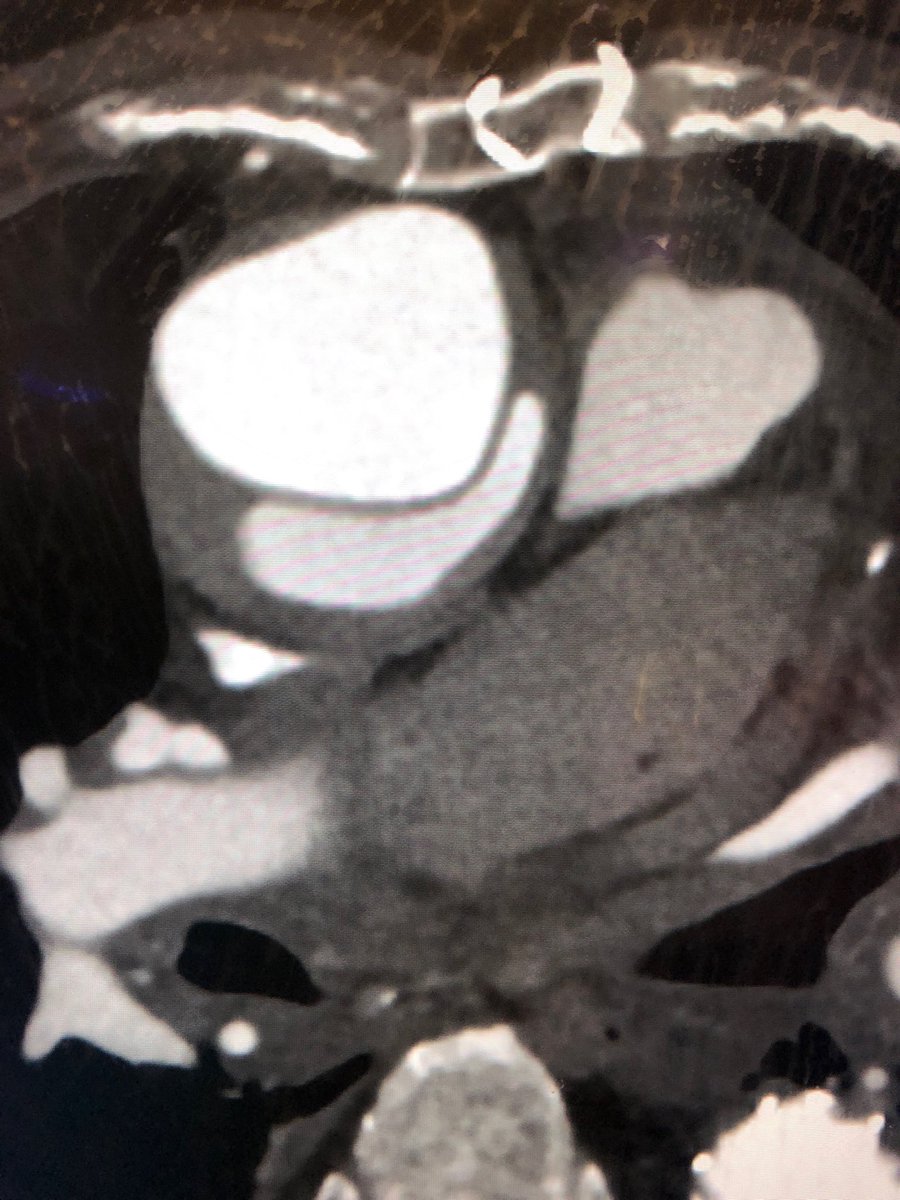

@DrAliAzizzadeh @CedarsSinai Beautiful 1 year follow up in a prohibitive risk patient with a commercially available device. Great work. Thank you for leading the way.

Emergency #TEVAR for #ruptured #typeA #dissection and #aneurysm in #nonagenarian. 1 year follow up #CT shows #healed #aorta #VascularSurgery @CedarsSinai